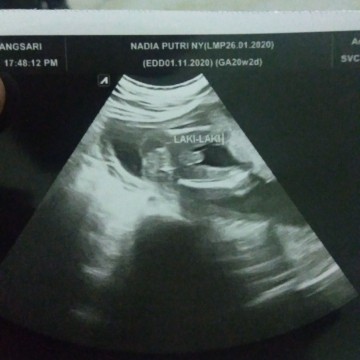

HPL 27 oktober- 2 November

Alhamdulillah ,begini ya rasanya mengandung Rasanya seneng,bahagia bgtt bersyukur diusia muda udah dikasih kepercayaan yang luar biasa ๐ค pertama kali USG pas umur kandungan 6 Minggu 3 hari, USG kedua 21 Minggu dan si utun langsung nunjukin jenis kelaminnya ๐คญ saat di USG juga terasa gerak2 dan ternyata kepalanya lagi nyundul2 โค๏ธ Seneng bgt setiap utun gerak2 ,berasa punya temen kalo suami lagi kerja๐ค